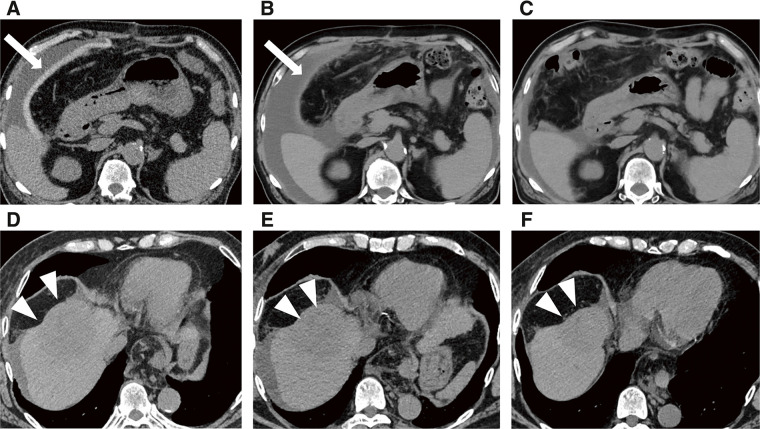

Case presentation: We report the case of a 77-year-old male patient diagnosed with a 6 cm HCC in segment 8, accompanied by impaired liver function, precluding hepatic resection. PBT was planned; however, because of the proximity of the gastrointestinal tract to the tumor, spacer placement was deemed necessary, and a bioabsorbable polyglycolic acid spacer was placed, followed by PBT. Owing to the sufficient space provided by the spacer, curative doses of PBT could be delivered to the tumor, and the patient survived for 26 months after spacer placement surgery without any sign of recurrence.